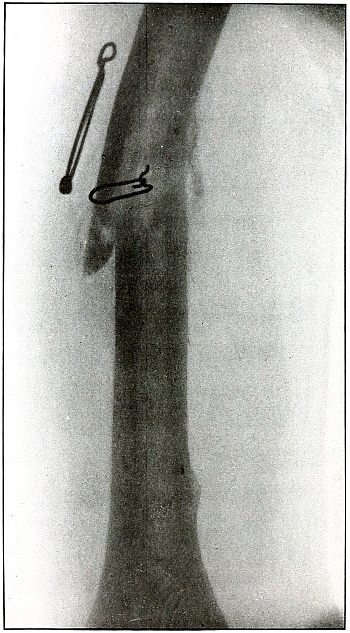

Rifle—Plate 28.

UPPER EXTREMITY.

Gunshot Fracture of the Radius.

The course of this bullet was anteroposterior and diagonally from

above downward through the shaft, punching out one side of the shaft

and effecting a diagonal fracture through the bone with only slight

displacement. The wound was infected.

The radiograph was taken during the course of treatment, after the

several small fragments found by the punched-out portion of the bone

were removed. A small drainage tube is in the wound, but the size of

the forearm shows that the reaction is very moderate.

The treatment is that of a simple fracture, except for the indications

to be met in the control of infection.

Results are good.